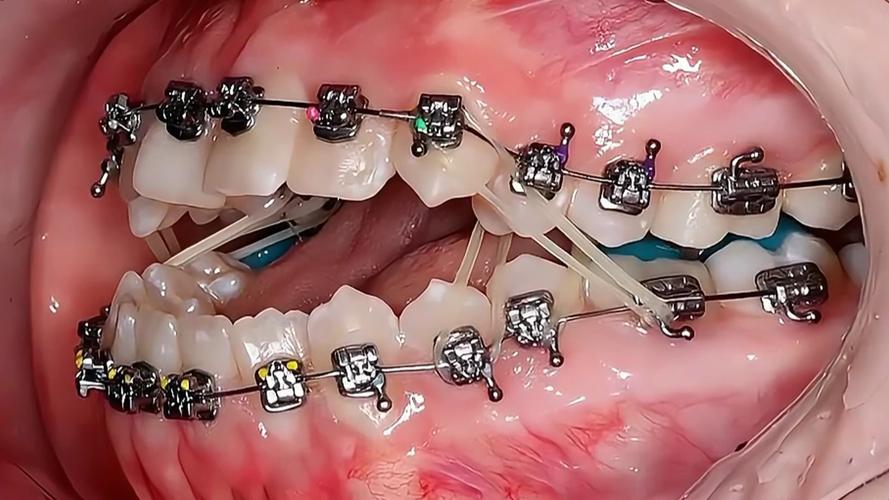

在北京进行隐形矫正,通常需经历系统化的流程,初诊阶段,医生会通过口腔检查、X光片(全景片、头颅侧位片)、CBCT(三维影像)等全面评估牙齿、颌骨、牙周状况,结合患者需求初步判断是否适合隐形矫正,若符合条件,下一步是数据采集:通过口内扫描仪获取牙齿三维数字模型,替代传统取模的 discomfort,精度更高且更高效,随后,医生利用专业软件进行方案设计,包括牙齿移动步骤、矫正周期、预期效果等,并与患者沟通确认,确保方案符合其预期,方案确定后,矫治器厂商会根据数字模型定制一系列透明牙套,通常每1-2周更换一副,通过持续、轻微的力引导牙齿移动至目标位置,整个矫正周期因人而异,一般需1-3年,期间需定期(每4-6周)复诊,医生会检查牙齿移动情况,调整方案或更换下一副牙套,矫正结束后,需佩戴保持器防止牙齿复发,保持器种类有透明压膜保持器、 Hawley保持器等,具体选择需遵医嘱。